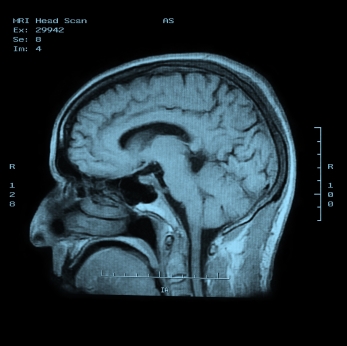

Диагноз устанавливается на основании клинической картины;  компьютерной и магнитно-резонансной томографии;

электроэнцефалографического исследования; биохимического исследования ликвора. Целесообразно проведение консультаций  невропатолога, психиатра, геронтолога.

Медицинские процедуры, проводимые при заболевании болезнь альцгеймера: Биохимический анализ крови, Клинический анализ крови, Спиральная компьютерная томография, Магнитно-резонансная томография, Биохимический анализ ликвора, Консультация невролога, Консультация психиатра, Консультация геронтолога